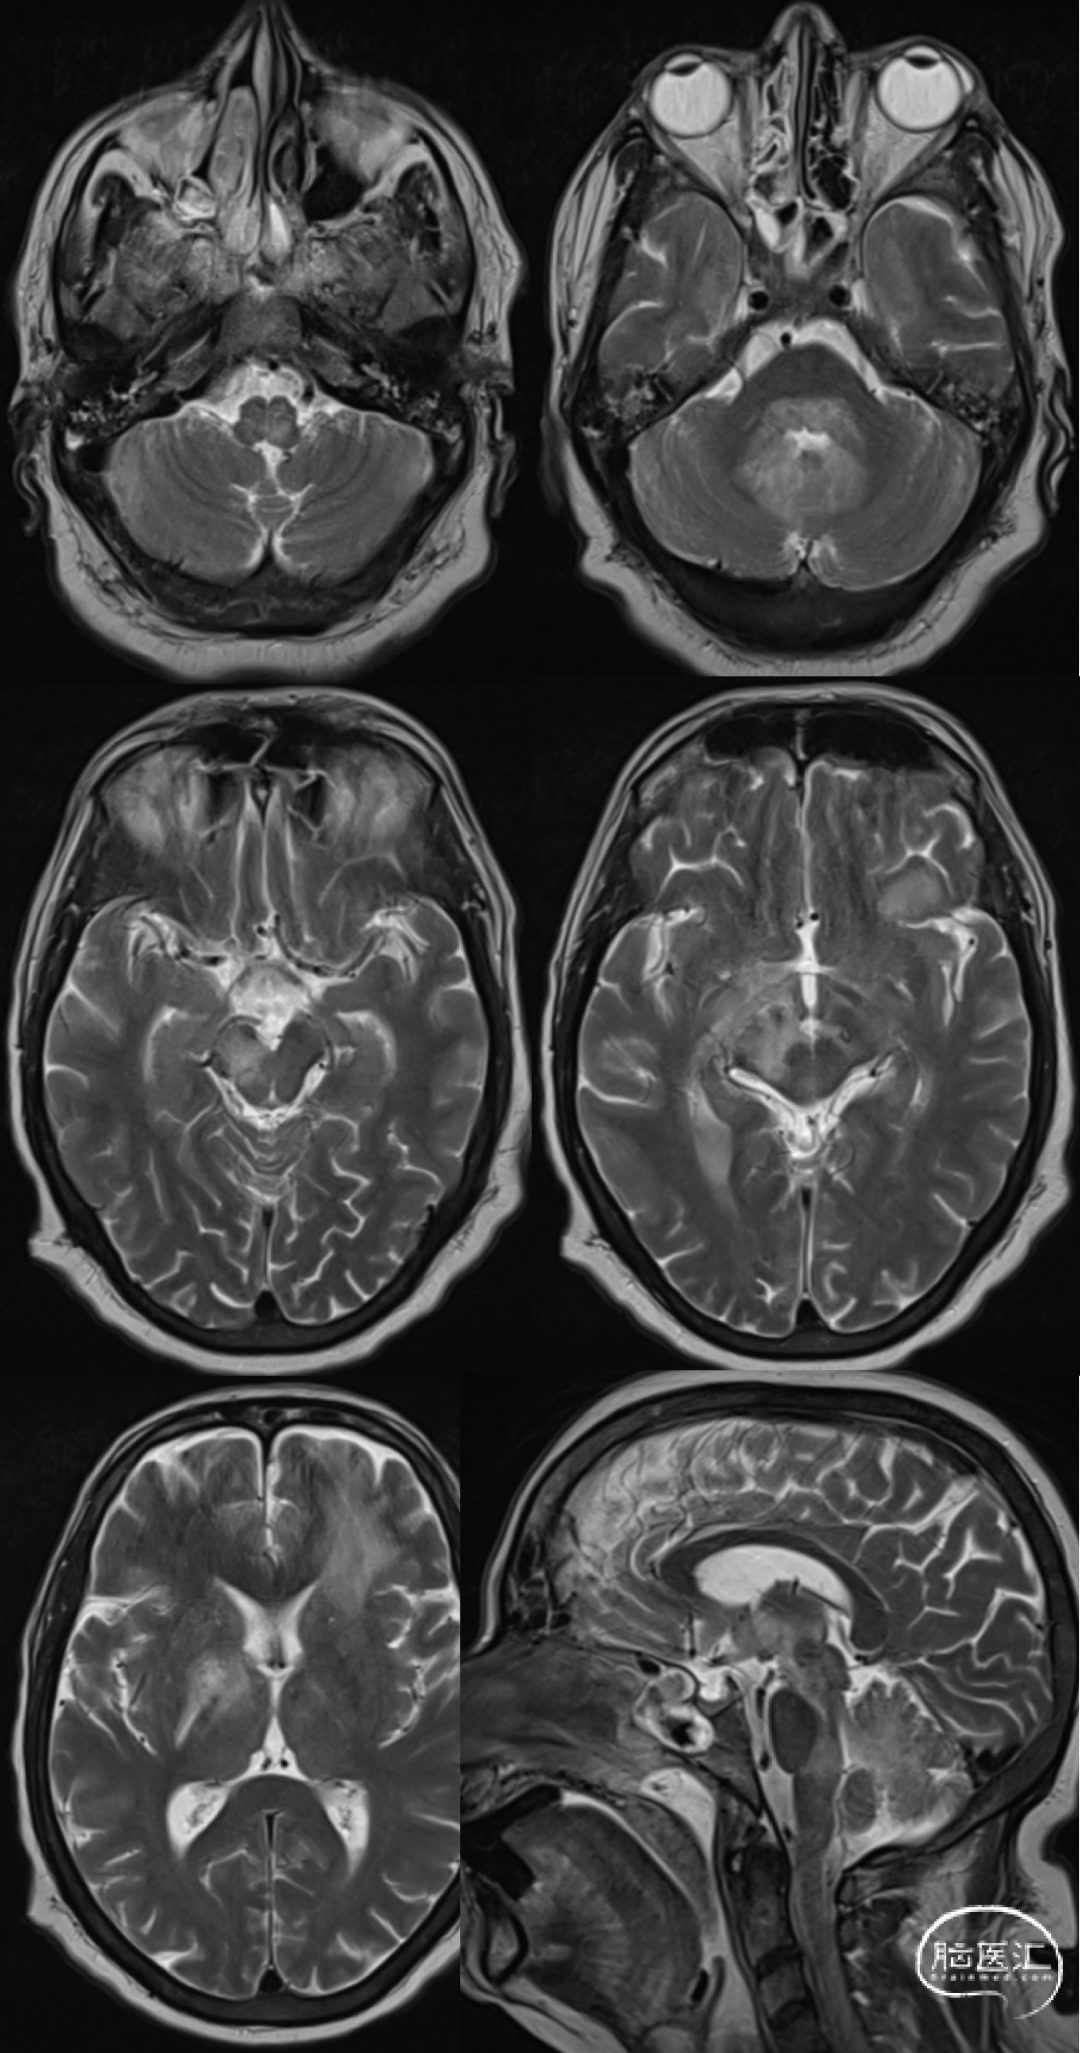

男,55岁,发热15天,精神异常2天。

菱形脑炎是指影响后脑(脑干和小脑)的炎症性疾病,病因多种多样,包括感染、自身免疫性疾病和副肿瘤综合征,单核细胞增生李斯特菌被认为是最常见的病因。菱形脑炎的发病率和死亡率很高。